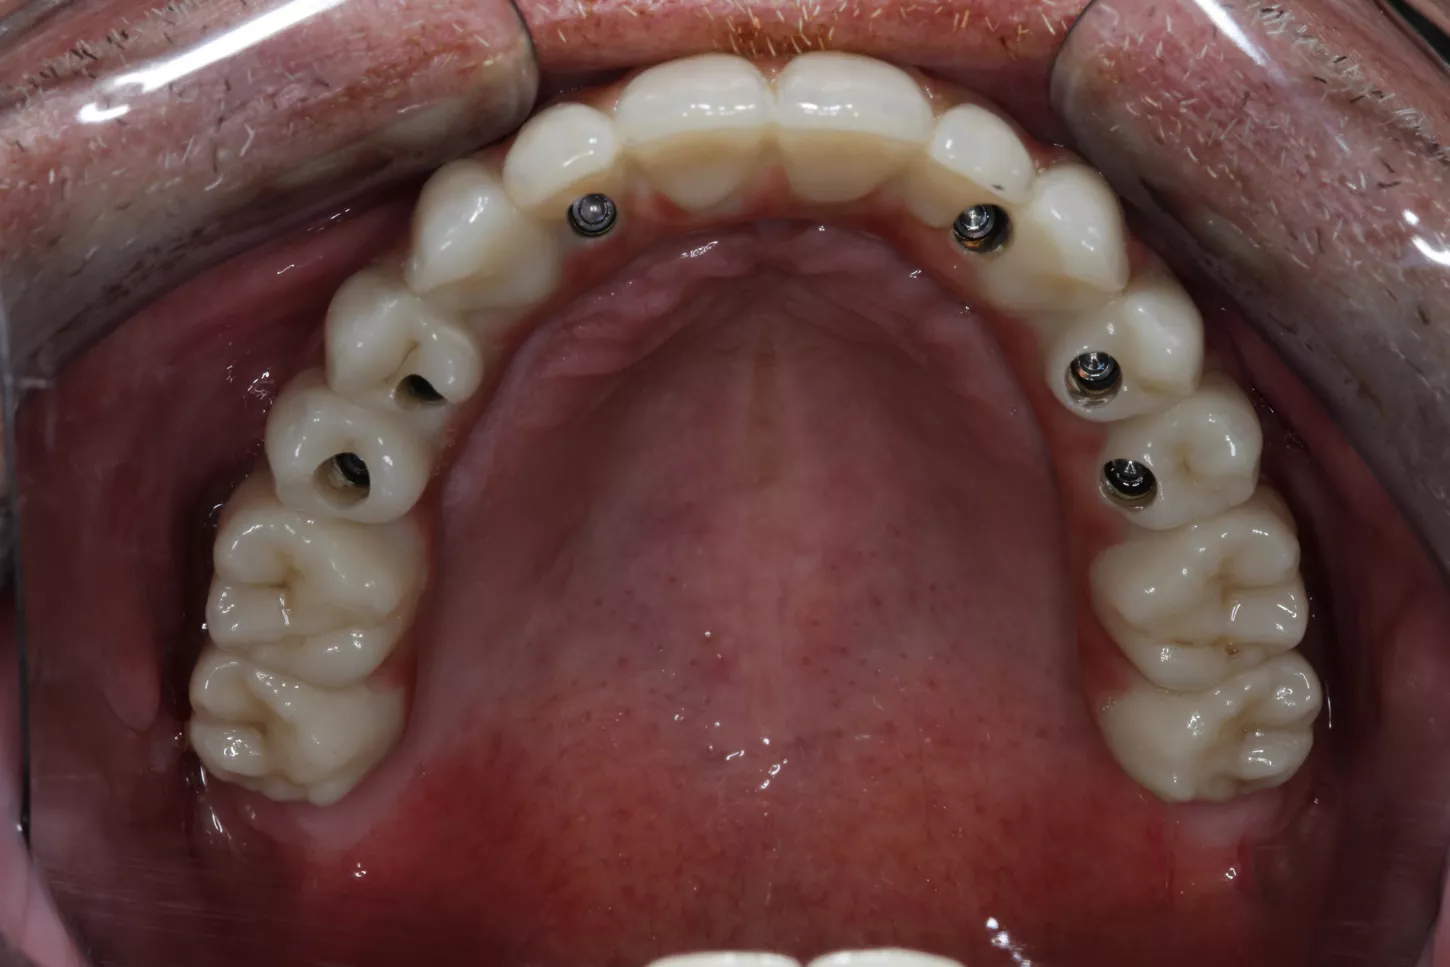

20a. 20b. In this clinical case, and as a novelty, we were able to screw both structures directly to the implants, since, the angled chimneys were incorporated in the titanium structure itself, in this case anodized to improve the final aesthetics.

20a

20b